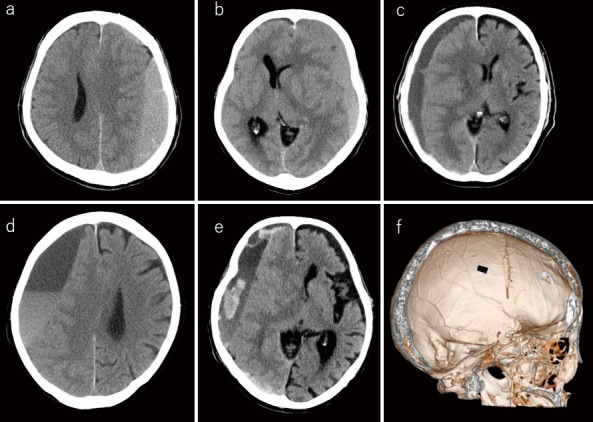

慢性硬膜下血肿是神经外科领域的一种常见疾病,在老龄化社会中,病例数预计将继续增加。在我院,微创经皮硬膜下穿孔(青木法)是一线治疗方法。我们调查了与青木法相关的复发率、复发相关因素和并发症风险。在2007年6月至2020年12月间采用青木法治疗的病例中,纳入了383例(431例)病灶,可以进行图像分析和复发追踪。根据患者的术前背景(性别、年龄、服用抗血小板和抗凝药物的历史、术前神经学表现、影像学表现(术前血肿体积和血肿密度)、手术细节、术后合用药物情况),回顾性分析其复发率、复发相关因素、并发症风险。复发率为23.7%,与钻孔血肿冲洗的复发率相同。多因素分析显示,年龄和术前血肿量大与复发有关。3例术后硬膜外血肿1例,硬膜下血肿2例需开颅。需要额外手术的并发症发生率约为1%,与钻孔灌洗相当。青木方法是有效的,因为它是微创的,治疗效果相当于钻孔冲洗,这是目前的标准护理。

Chronic subdural hematoma is a common disease in the field of neurosurgery, and the number of cases is expected to continue increasing in an aging society. At our hospital, minimally invasive percutaneous subdural perforation (the Aoki method) is the first-line treatment. We investigated the recurrence rate associated with the Aoki method, factors related to recurrence, and the complication risks. Among the cases treated with the Aoki method between June 2007 and December 2020, 383 (431 lesions) for which image analysis and recurrence tracking were possible were included. On the basis of the preoperative patient background (sex, age, history of taking antiplatelet and anticoagulant drugs, preoperative neurological findings, imaging findings (preoperative hematoma volume and hematoma density), surgical details, and postoperative use of concomitant drugs), we retrospectively analyzed the recurrence rate, factors related to recurrence, and complication risk. The recurrence rate was 23.7%, which is within the same range as that of burr-hole hematoma irrigation. Multivariate analysis showed that age and a large preoperative hematoma volume were associated with recurrence. One of the 3 cases with postoperative epidural and 2 of the 3 cases with subdural hematomas required craniotomy. The incidence of complications requiring additional surgery was approximately 1%, which is comparable to that of burr-hole irrigation. The Aoki method is efficient because it is minimally invasive and has a therapeutic effect equivalent to that of burr-hole irrigation, which is the current standard of care.